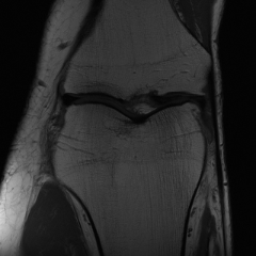

Notably, X-Diffusion achieves sota dB for a few input slices while baselines require more than 60 input slices to achieve similar performance (Figure 7). The margin is more than 12 dB PSNR for the 1-slice input in both the BRATS and the UK Biobank benchmarks (see Table 1 and Figure 6). For reference, two randomly sampled MRIs from the UK Biobank would have a PSNR of 15.95 dB 0.36 (on 4800 randomly sampled examples). The slices from 3D reconstructed volumes at varying depths and axis of rotation visually match the ground truths (see Figures 5 and Figure 4). We also plot the error map (Figure 4) of such X-Diffusion generations to highlight the differences with the ground truth MRIs.

One way to test the generalization capability of the trained X-Diffusion is to test it on a completely different domain from an MRI dataset not seen during training. We report the single-slice results on the test set of knees from NYU fastMRI [33, 80], using the X-Diffusion trained on the BRATS brain MRIs. The test PSNR result is 34.17 and an example is shown in Figure 8. It shows how successfully X-Diffusion can generate knee MRIs (out-of-domain) despite being trained on brains.